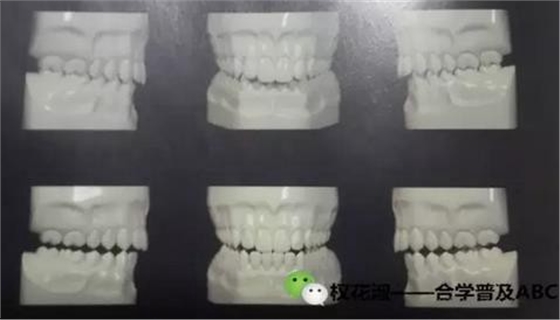

大家看這兩張圖,有什么區(qū)別,做一個(gè)比較。

以上給大家是一個(gè)靜態(tài)的咬合關(guān)系,只是一個(gè)正面的圖,不要在腦海里只想到正面,還要考慮側(cè)面,還要從里側(cè)觀察,當(dāng)然從舌側(cè)觀察咬合關(guān)系需要在模型上觀察

再看這張圖,這是我的老師的一本專著當(dāng)中一張插圖,詮釋的是尖牙保護(hù)合,我們牙齒的一個(gè)動(dòng)態(tài)的接觸關(guān)系,是一種邊緣運(yùn)動(dòng)的咬合關(guān)系,看下圖三個(gè)模型,中間是前伸運(yùn)動(dòng)時(shí)后牙的咬合分離,左側(cè)的是向左側(cè)方運(yùn)動(dòng)時(shí)只有尖牙接觸,其他牙齒咬合分離,右側(cè)是向右側(cè)方運(yùn)動(dòng)時(shí)只有尖牙接觸,其他牙齒咬合分離。這是理想狀態(tài)下的咬合關(guān)系,那在非理想狀態(tài)下咬合的側(cè)方運(yùn)動(dòng)是怎么的接觸關(guān)系呢。

這三張圖表達(dá)的是通常所說的組牙功能,在做側(cè)方運(yùn)動(dòng)時(shí)除了尖牙以外的牙齒有接觸,(或者尖牙沒有接觸),其他牙也有接觸的多組牙齒接觸的咬合狀態(tài),這種動(dòng)態(tài)咬合關(guān)系,歸類為非理想的一種動(dòng)態(tài)咬合關(guān)系。